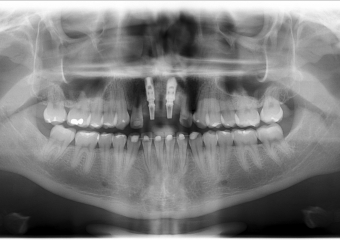

Rx Panorâmico dos implantes com prótese provisória